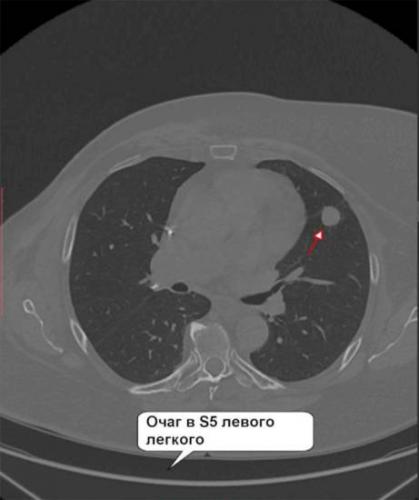

Как очаги в легких выглядят на снимке КТ?

Чтобы человек несведущий смог разобраться в результатах КТ, следует знать о нюансах чтения снимков. Рассмотрим самые актуальные:

- Очаговые образования представляют собой участки белого цвета на черном фоне (на снимке-негативе). В реальности пораженная область, скорее всего, имеет более темный цвет, чем здоровые ткани легкого.

- Если врач заметит на снимке участки кальцинирования или обызвествления (капсул, пропитанных солями кальция) вокруг очага, это может быть признаком доброкачественности образования. Кальцинаты по цвету похожи на кости скелета, видимые на этом снимке. Такие явления часто обнаруживаются после затяжных простудных заболеваний, бронхитов или уже излечененного туберкулеза и представляют собой некий шрам на легких. Пациента с образованием, на котором заметны признаки кальцината, пульмонологи обычно просят раз в полгода делать контрольные снимки.

- В случае, когда образование представляет собой так называемое «облачко» или очаг по типу «матового стекла», требуется более предметное обследование. Внешне оно выглядит как затуманенная область с размытыми границами. В ряде стран пациентам с такими образованиями сразу рекомендуется операция, даже если оно не растет. Уже доказано, что в 80% случаев такие очаги являются предраковым состоянием легких. Альтернатива немедленной операции — постоянное наблюдение с контрольными снимками раз в полгода-год.